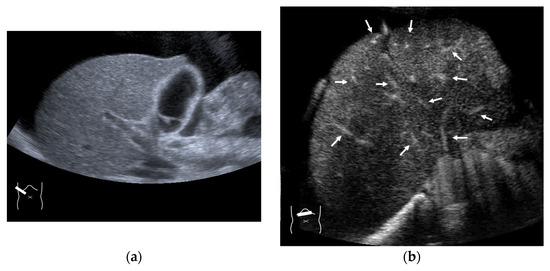

3.1. Hepatocellular Carcinoma (HCC)

3.2. Liver Metastasis

3.3. Benign Liver Tumors

4. HV Hemodynamic Changes (Vascular Shunts) in Non-Tumor-Related Livers